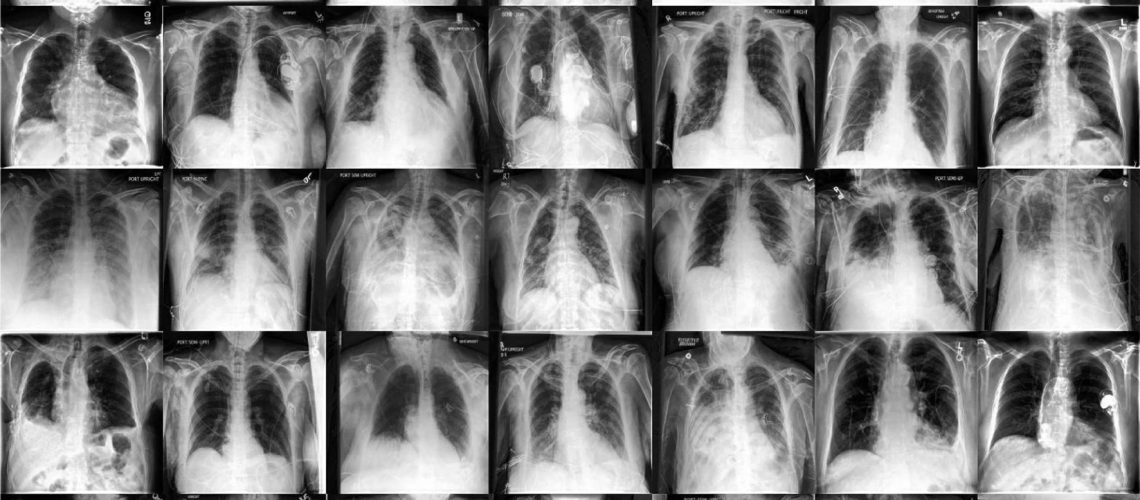

החוקרים השתמשו בשני מערכי רדיולוגיה ציבוריים גדולים, CheXpert ו-ChestX-ray, כדי ליצור מודלים יצירתיים ואבחונים לצילומי חזה. לאחר אימון על 201,055 מקרי רנטגן של החזה, רופאי עור העריכו את יכולתו של המודל ללכוד מאפיינים ראשוניים על 488 תמונות סינתטיות משיעורים רגילים ובסיכון גבוה. הם העריכו את איכות התמונה כדי להציע אבחנה של עד שלוש מתוך כ-20,000 המחלות הנפוצות.

המחקר מראה כי מודלים של דיפוזיה עשויים ללמוד הגדלות מציאותיות מנתונים בצורה יעילה בתווית, מה שהופך אותם לגמישים והוגנים יותר מבחינה סטטיסטית הן בהפצה ומחוצה לה. שילוב של נתונים סינתטיים ונתונים בזמן אמת יכול להגביר במידה ניכרת את דיוק האבחון ולהקטין את פער ההגינות בין איכויות שונות במהלך שינויים בהפצה.

הגדלת צבע על גבי דגימות שיוצרו הניבו את הביצועים הטובים ביותר בסך הכל, עם שיפורים יחסיים של 49% לעומת מודלים בסיסיים ושיפור של 3.2% לעומת דגמים עם הכשרה להגדלת צבע בבית החולים הנבדק. המחקר הראה שתמונות סינתטיות העלו במידה ניכרת את ה-AUC הממוצע עבור חמש מחלות, בעיקר קרדיומגליה ו-OOD. פער ההוגנות הנשי הצטמצם ב-45%, בעוד פער ההוגנות הגזע הצטמצם ב-32%. שילוב של הגדלות היוריסטיות עם טכניקות מבוססות נתונים סינתטיות כמו 'התניה של תווית' ו'התניה של תווית ומאפיינים' הגביר את רגישות המודל מבלי לוותר על הגינות, מה שהביא לרווחים ניכרים בתרחישי OOD.